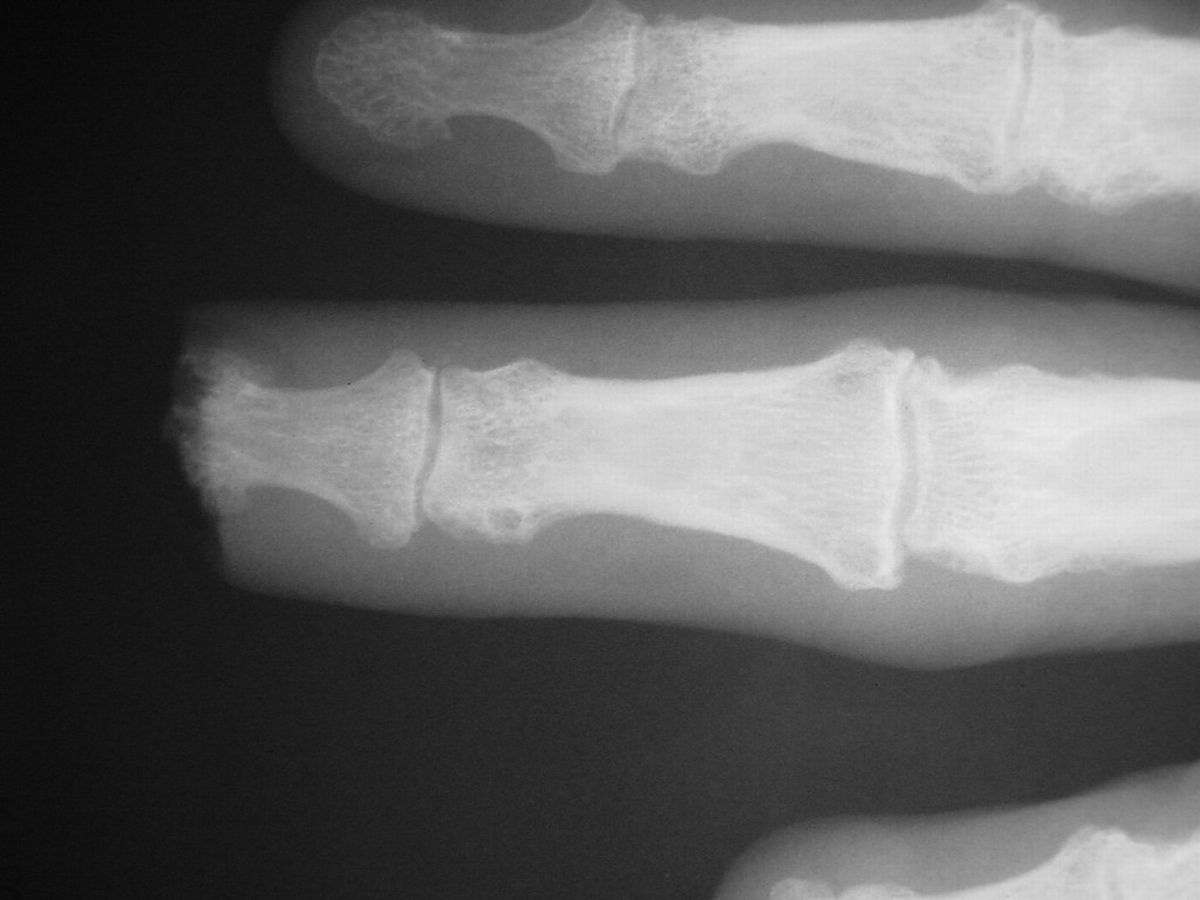

| Case

3. This gentleman sustained partial amputations of all fingers in an industrial press. His index finger was the only digit with a potentially salvageable fingertip. |

| Distal phalanx

fracture stabilization. Pins were placed to protrude

proximally in anticipation of flap cover. |